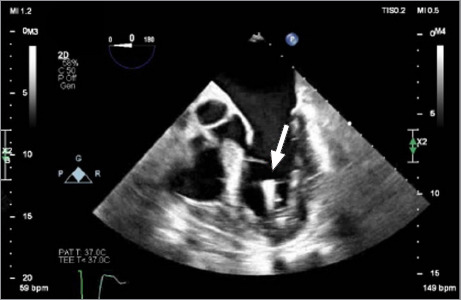

Micra装置是一种通过股静脉经导管入路植入右心室的无铅起搏器。使用无导线起搏器有几个适应症和优点,该设备在心脏病学领域的作用可能会继续增加。这篇文章提出了一个罕见的并发症的情况下,可能是由于无意中放置装置在左心室跨越一个未确诊的卵圆孔未闭。

The Micra device is a leadless pacemaker implanted in the right ventricle via a femoral vein transcatheter approach. There are several indications for and advantages to using a leadless pacemaker, and the device's role in the field of cardiology will probably continue to increase. This article presents the case of a rare complication probably due to inadvertent placement of the device in the left ventricle across an undiagnosed patent foramen ovale.